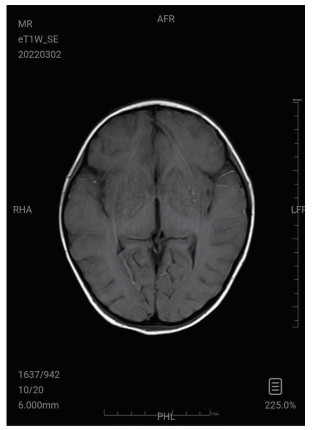

| 图 3 3月2日颅脑MRI |

图 1为颅内弥漫脑实质肿胀,脑沟脑回显示不清,脑室受压,部分脑沟内可见高密度影,右侧小脑幕密度增高。中线结构居中。副鼻窦内见软组织密度影。图 2为大脑皮层、小脑及脑干形态肿胀,呈稍长T2信号影,有类似束带征。图 3为后颅窝去骨辨减压+小脑部分切除术后复查: 脑疝征象明显好转。